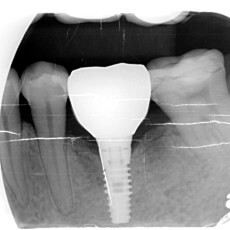

我們會將適當尺寸的人工植體植入計畫好的位置中,植體將如同自然牙的牙根,扮演著支持未來牙冠的角色.手術都在局部麻醉下進行,所以過程幾乎是無痛的.如果您特別敏感或容易緊張,我們也提供口服鎮靜劑或舒眠鎮靜的選項,幫助您克服對於手術的恐懼.

縫線將在術後7-14天拆除,之後依傷口復原情形,只需每個月定期回診追蹤,植體依照骨質情況,在2-6個月骨整合完成後,將進入贋復階段.

經由全口電腦斷層檢查,可以明確的知道植牙區骨頭的3D結構,從而了解您是否適合植牙,判斷根據可以參考植牙區需不需要補骨補肉

• 精準定位:診所備有目前全球頂級的德國KaVo電腦斷層,您不須再到影像中心拍攝,同時可以做到手術中拍攝定位,最佳化植體位置,避免植體位置不佳或是損害神經的風險.